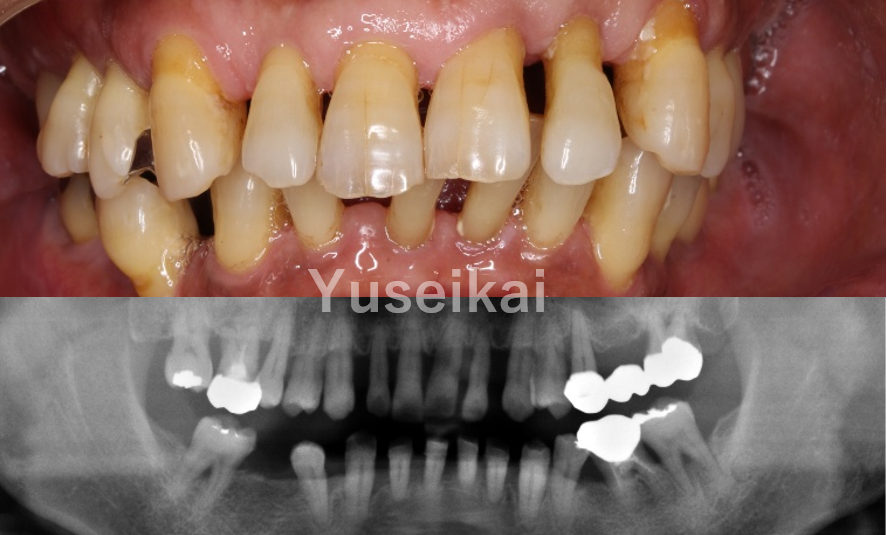

抜歯を伴う症例や、すでに多くの歯を失ってしまっている症例は、インプラント治療の難易度が高いとされています。当院では、そういった難症例に対しても治療を行うことが可能です。顎の骨が不足している場合でも、サイナスリフトなどの骨造成を行うことで、インプラント治療を実施することができます。他院でインプラント治療が困難だった方も、当院では治療可能な場合がありますので、まずはご相談ください。

インプラント治療を行ううえで、むし歯や歯周病が進行している場合や、歯が割れている場合等は、抜歯が必要になることがあります。その際、患者様の口腔内の容態に応じて適切な処置を行います。